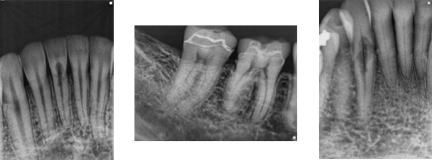

Radiographic Presentation

ECIR lesions are usually missed until they have reached a class III or IV status, appearing as a moth eaten radiolucency with ragged borders (Figure 7). The communication with the periodontal tissues may be pinpoint or cavernous. Larger lesions may also contain hard tissue and have a trabecular bone type appearance. The pattern of resorption is unique as it typically progresses vertically alongside the pulp without penetration(Figure 8). A thin layer of dentin and predentin usually remains intact and walls off the pulp from the invasive fibrovascualar tissue. As a result most teeth with ECIR lesions contain vital pulp tissue and periapical tissues appear normal. Again the resorption process is due to rogue clastic periodontal host cells and does not inherently involve acute or chronic inflammatory cells unless microorganisms have secondarily invaded the space.

Figure 7- Radiographic appearance of ECIR. From left to right, #’s 24, 30, and 27. All cases are from patients of Tri-City Microendodontics.